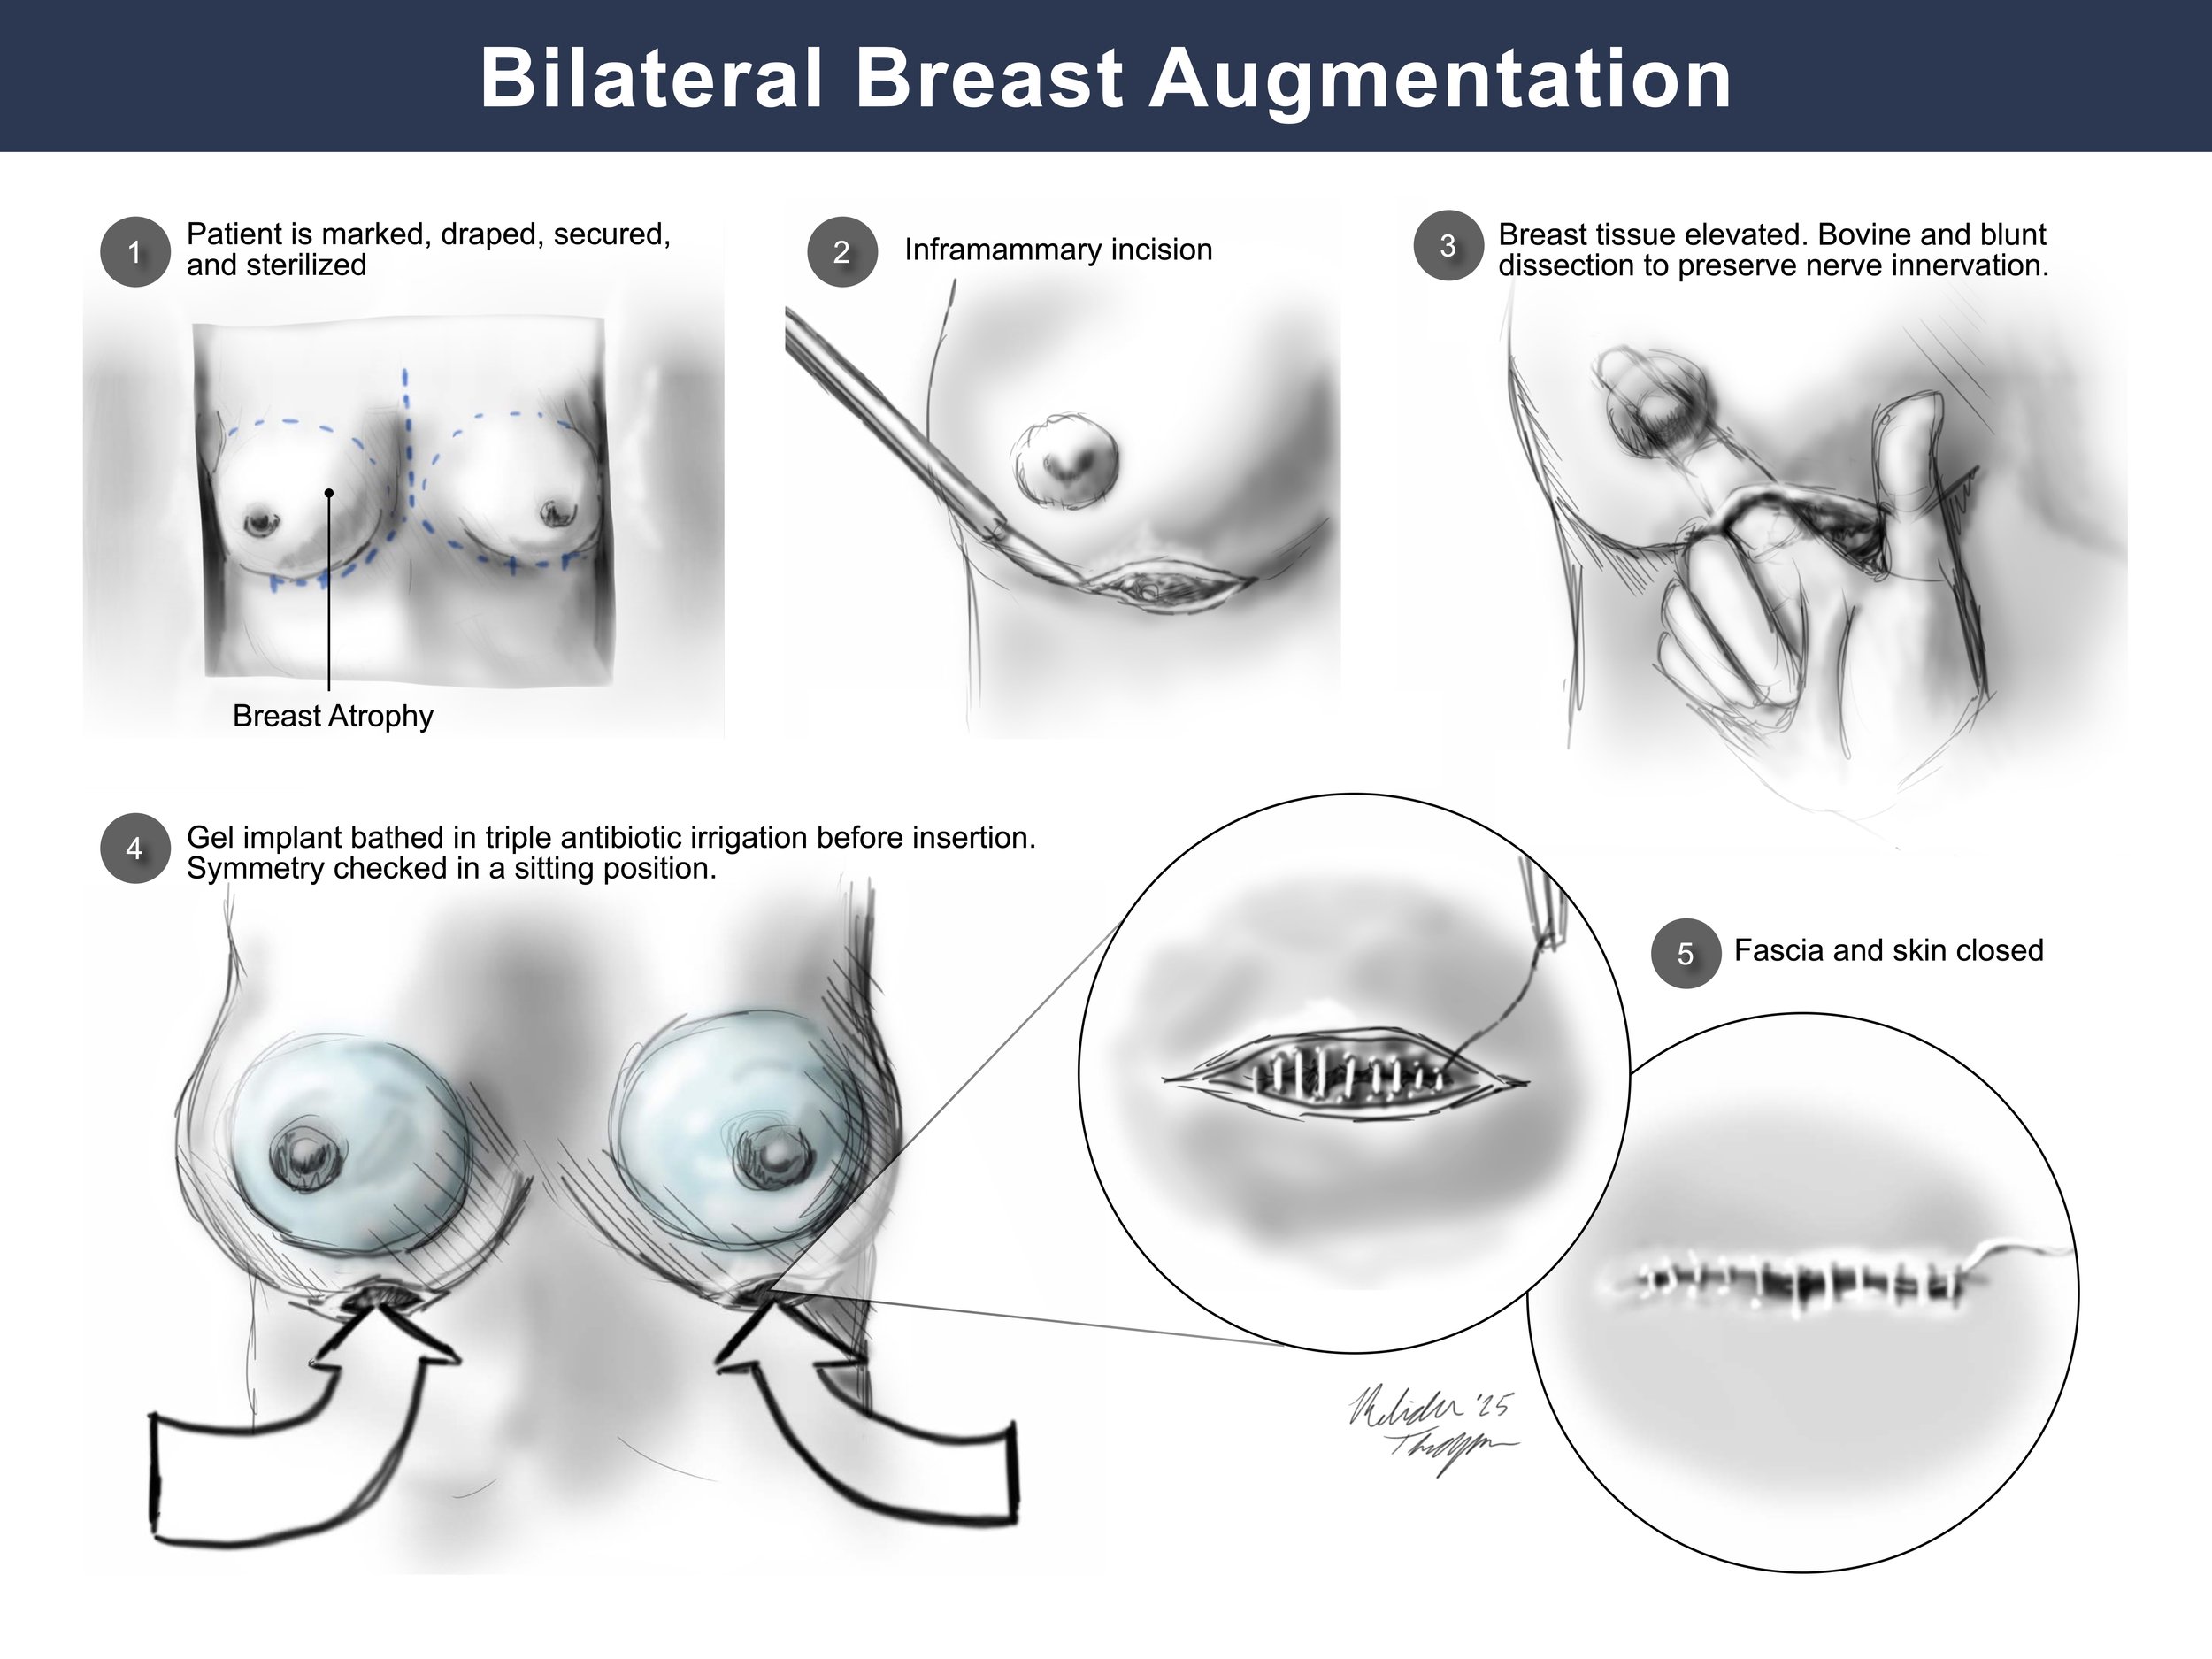

Medical Legal Illustration

Medical Illustration is important in the courtroom for many reasons including communicating scientific information for a lay audience, highlighting injury or anatomical differences, or simply representing potentially disturbing images in a more digestible way. Legal illustrations must be accurate, but still serve to help tell the defendant or plaintiff’s story.

Additional Medical Legal Illustrations

Bilateral Breast Augmentation: Surgical Exhibit Mockup